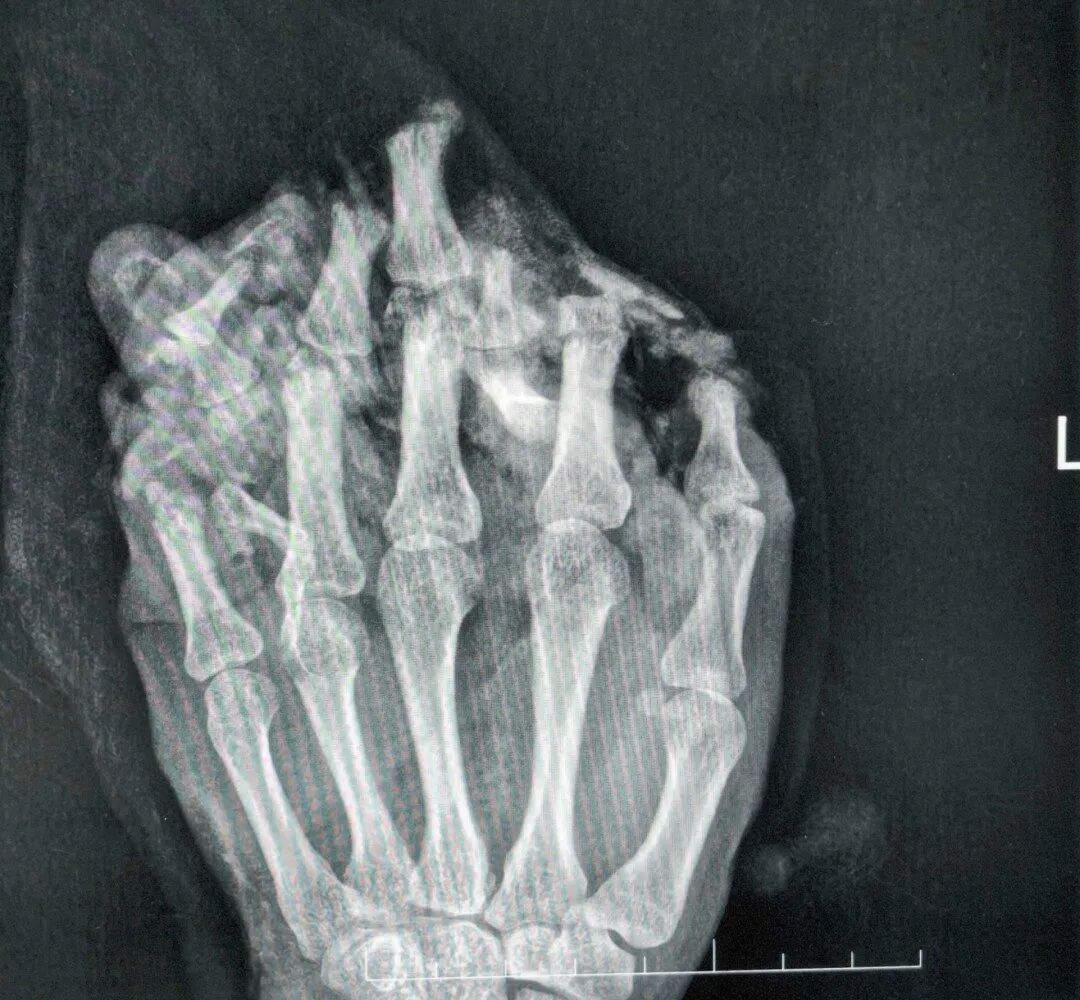

医师会诊他为:1.左手掌、手背,示指中指环指小指掌侧及背侧皮肤毁损脱套伤;2.左手掌、手背及各指肌腱神经血管挫伤;3.左手多发性洞开性指骨骨折伴毁损;4.左拇指小节指腹皮肤、软组织缺损;5.左拇指固有神经断裂;6.左拇指甲床裂伤。

病院赶紧为小王作念了手术,术中,医师们完成了绝对的清创,确立了骨折、断裂的肌腱与神经。

为遮蔽强大创面,医师启用了经典的“腹部带蒂皮瓣”,将断手“寄养”在了带有本身血供的腹部皮肤上,为后续系数确立提供了生活的泥土。